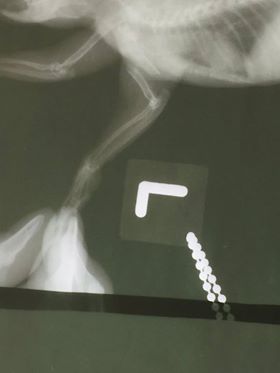

อาการ ขาหน้าซ้ายหัก ขาหลังทั้งสองข้างไม่มีการตอบสนอง

ภาพฟินฟินในวันแรกที่พาไปรักษาเนื่องจากแขนซ้ายหัก ส่วนขาเดินไม่ได้ทั้งสองข้าง

อาการบาดเจ็บและสภาพแผล

แขนหน้าซ้ายที่หัก ไม่สามารถต่อได้อีก